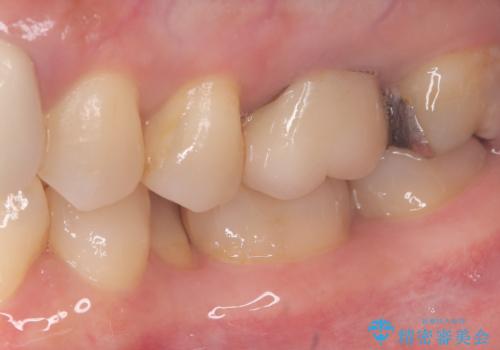

- 主訴:昔入れた銀の詰め物を白い物に替えて金属を無くしたい。

審美性、適合性の観点からセラミックインレーでのやり替えとなりました。

保険適用のメタルインレーを除去した際、下に広がっているカリエスも除去し形成印象を行いました。

セラミックインレーセット時はラバーダム防湿を行っています。